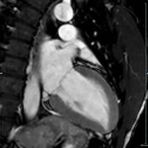

- kardiale Ischämiediagnostik mit medikamentöser Stress-MRT (Adenosin)

- Infarktnarbendarstellung/Vitalität

- Kardiomyopathien (z.B. Myokarditis, DCM, HCM/HOCM, Amyloidose, Sarkoidose)

- Klappenbeurteilung mit Phasenkontrastangiographie

- Tumoren Herz und Mediastinum

- Fehlbildungen

- MR-Angiographie zur Erfassung und Verlaufskontrolle von Aneurysmen der Aorta thorakalis und ihrer Gefäßabgänge